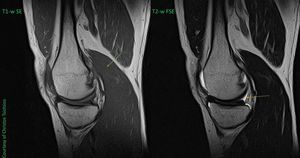

How can we identify a T1-weighted or T2-weighted image on MSK MR Imaging? Unfortunately, fat is not a good indicator because, due to J-coupling, it will be ("abnormally") bright on all FSE pulse sequences. The first key point is that fluids will be hyperintense on T2-w image (yellow arrow) and hypointense on T1-w image. The second key point is that muscles will be brighter on T1-w image (green arrow) compared to T2-w image.